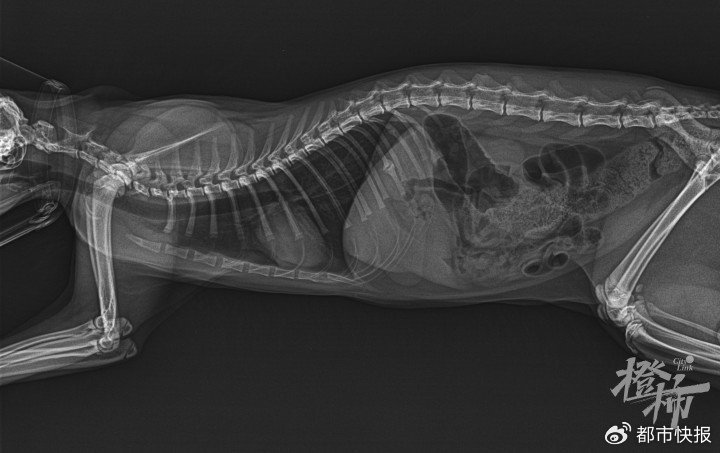

8月6日“白板”的拍片

“白板”在吸氧

8月6日中午,王小姐带“白板”去住所附近一家宠物医院,做了生化检查、拍片、血常规、猫BNP(结果显示异常)、吸氧、呋塞米注射,病情诊断为“心源性肺水肿”,花费1341元。这家医院无高压氧舱,建议转到另一家宠物医院。打车去的路上,“白板”就没了呼吸,送到后抢救10多分钟宣布死亡,病历上写着:“主要诊断:拟心脏病发作急性休克。”抢救花费300多元。